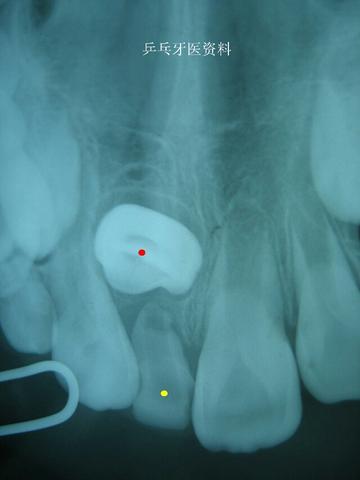

下面这2张图片显示一12岁患儿左下乳牙(黄点标记)根尖反复发炎导致对应恒牙(红点标记)水平阻生,不能正常萌出,后续经过一年时间的治疗才将这个恒牙牵引成功。

全景片示:左下乳牙牙根发炎导致恒牙不能萌出

牙片示:左下乳牙牙根发炎导致恒牙不能萌出